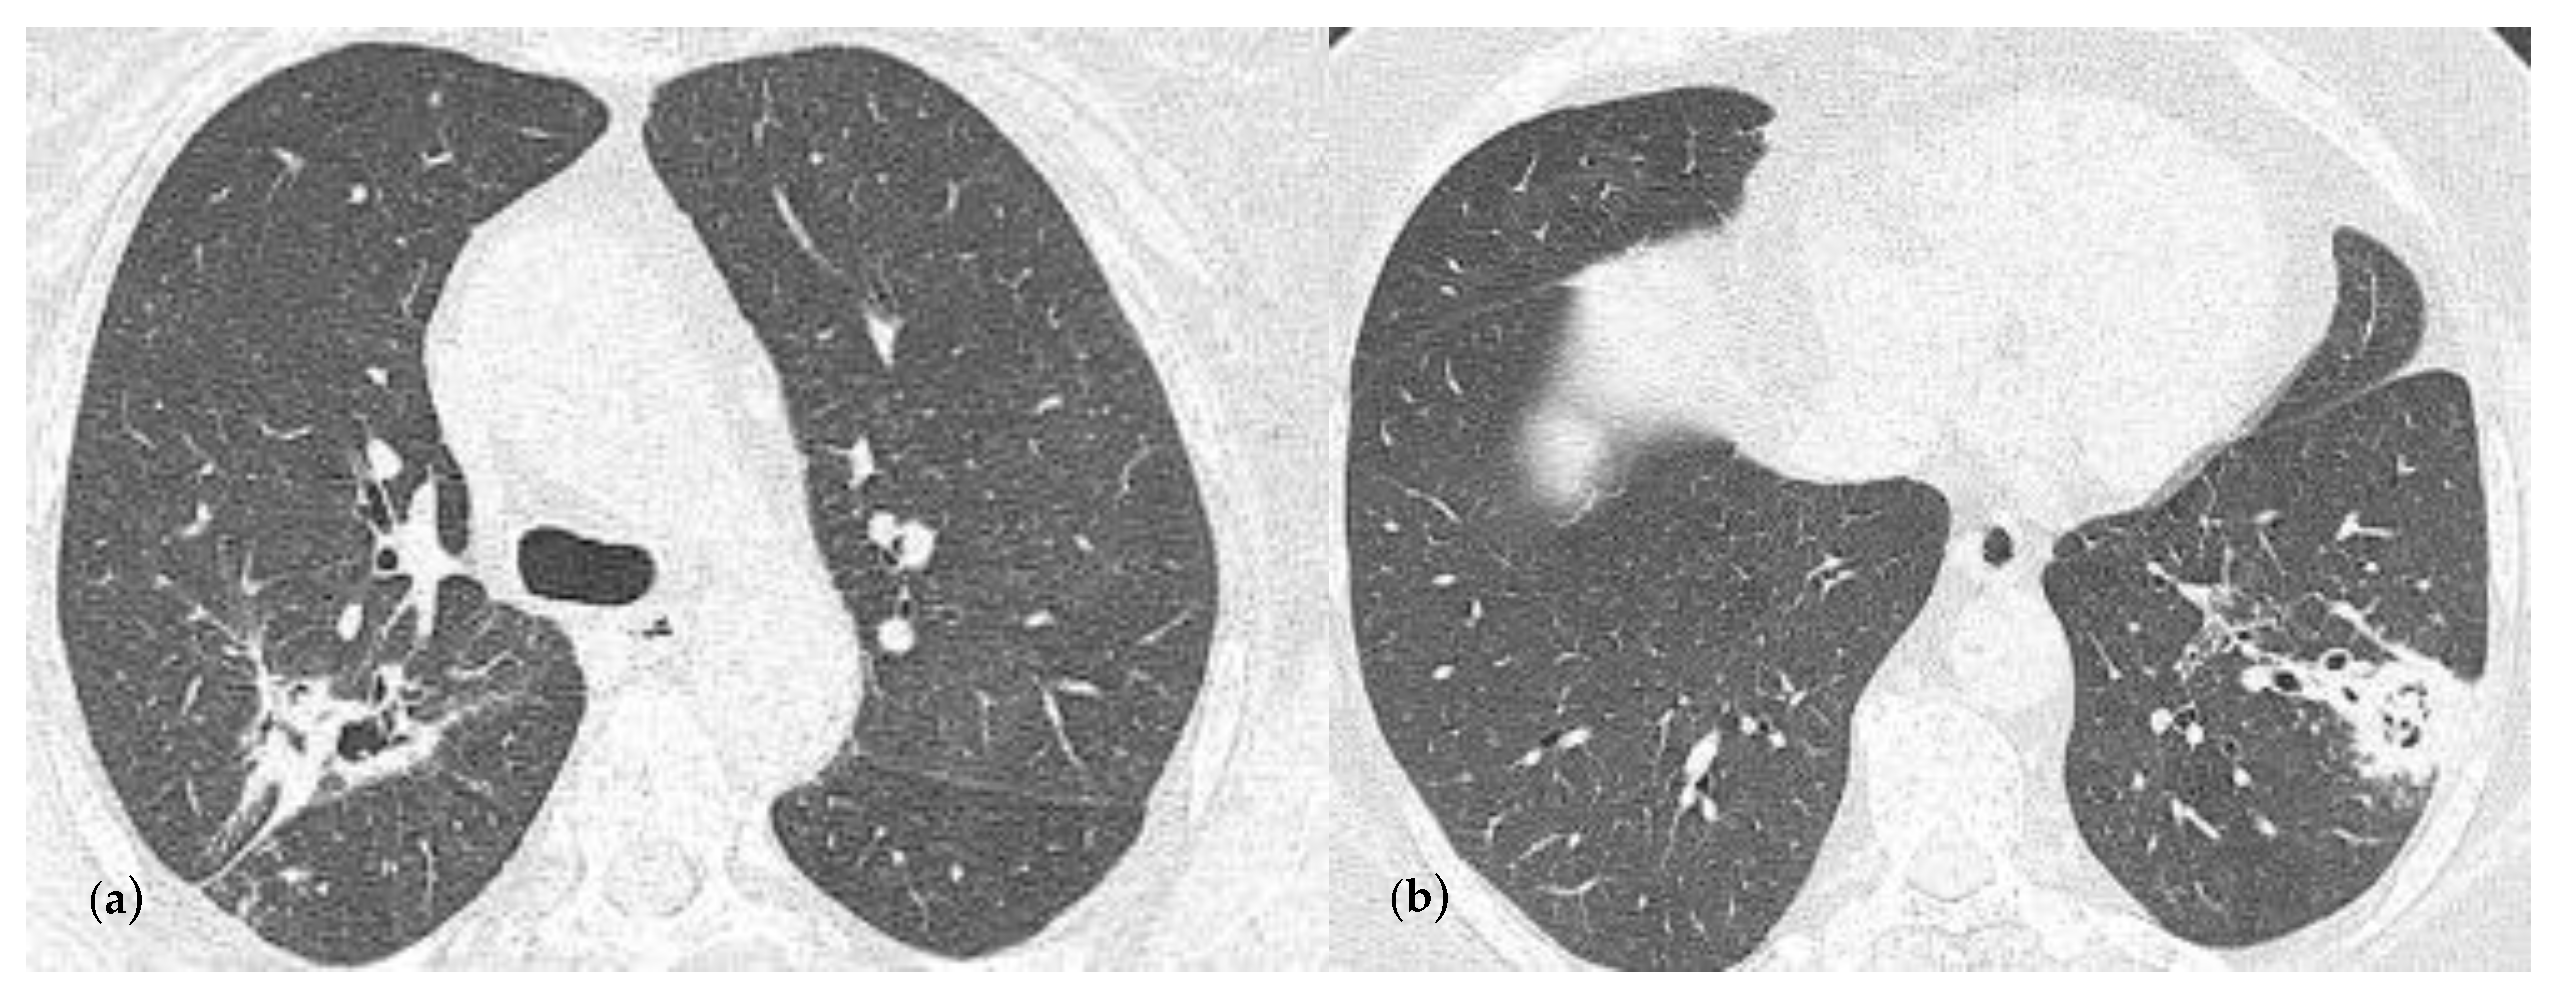

2.2. Blood Workup, Functional Tests, Bronchoscopy, and Radiological Findings

2.3. Treatment and Monitoring

2.4. Follow-Ups